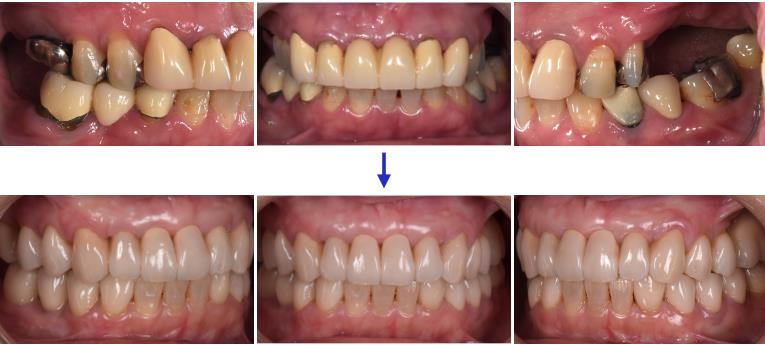

患者は40代女性で、上の歯が前に出ていることで噛みにくく、見た目も良くしたいとの理由で来院されました。奥歯の数は少なく、特に左上は大臼歯がありませんでした。上下の歯の真ん中のラインは大きくずれており、昔に入れた前歯の被せ物は変色し、審美障害を呈してました。(図1、2)

歯並びを理想的にデザインしたセットアップモデルを見ると、全体的な歯の移動量は2ミリ程度で小さく、本ケースではまず左上にインプラントを入れてから矯正を行いました。(図3)